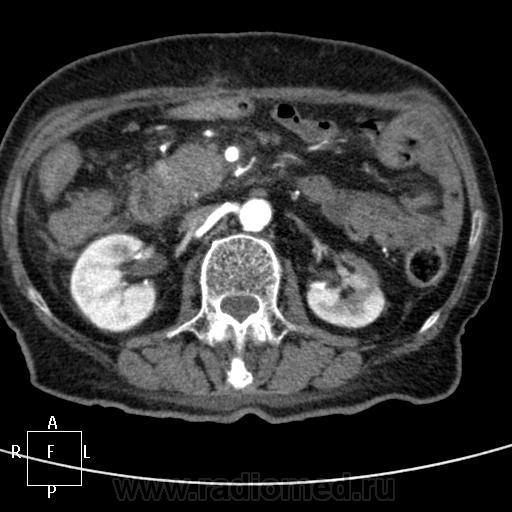

КТ поджелудочной железы. Пациентка 80 лет.

Упорные боли, кратковременно купируются ненаркотическими анальгетиками. Диастаза мочи 300. Кровь без особенностей. Псевдотуморозный панкреатит или опухоль? Опыта с панкреатитами - кот наплакал в знойный день))...

45 сек:

С левой почкой - кто такое видел? Атрофия средней трети и частично нижнего полюса, а в верхнем... помогите, пожалуйста!)) Вроде доброкачественное обызвествление. Не получилось напоить водой - несколько глотков и наотрез отказалась - тошнота. Поэтому 12-перстная безконтрастная практически.

На мой взгляд - опухоль головки ПЖ. Атроифя\ хоста и тела. Вирсунг расширен до зоны образования в головке - дальше четко не определяетя. Обычно при панкреатитах вирснуг хоть дефоримрованный но проходит через зону фиброзно-воспалиетльных изменений. Тут же похоже его обтурация.

На 45 секунде оразовние несколко гиподенсно по отношению к другой паренхиме (хотя и фиброз тоже такой будет).

Вообщим опухоль на мой взгляд головки ПЖ.

Согласен,кроме того,на 57-60 секундах в толще образования определяется ветвь верхней брызжеечной артерии.